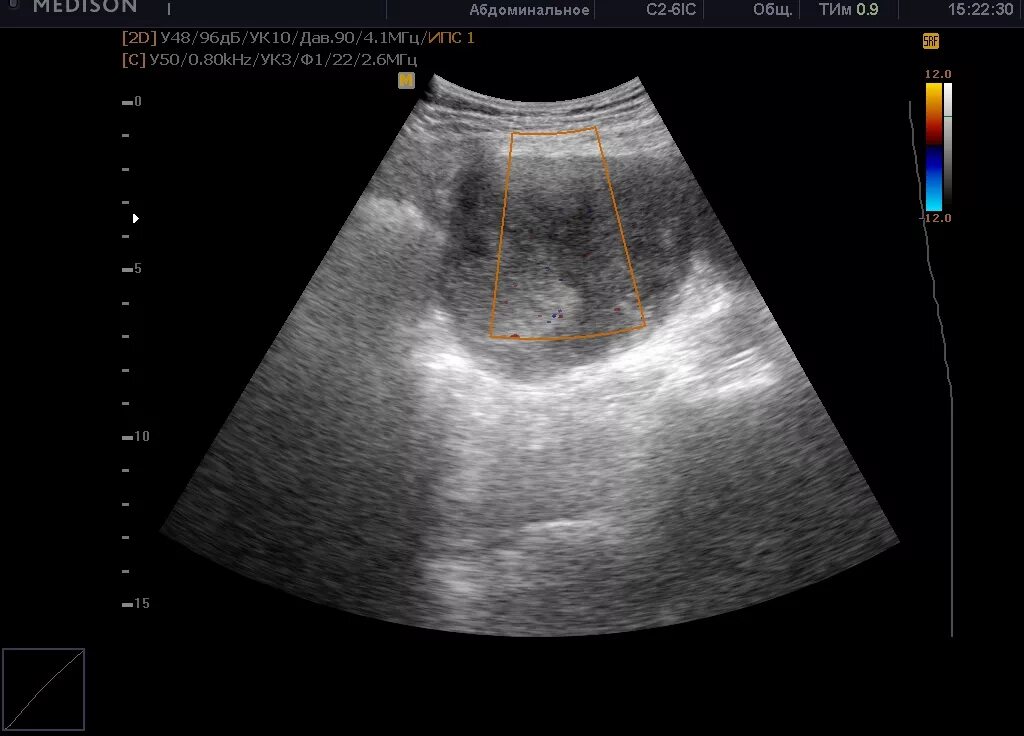

Узи сердца узи почек